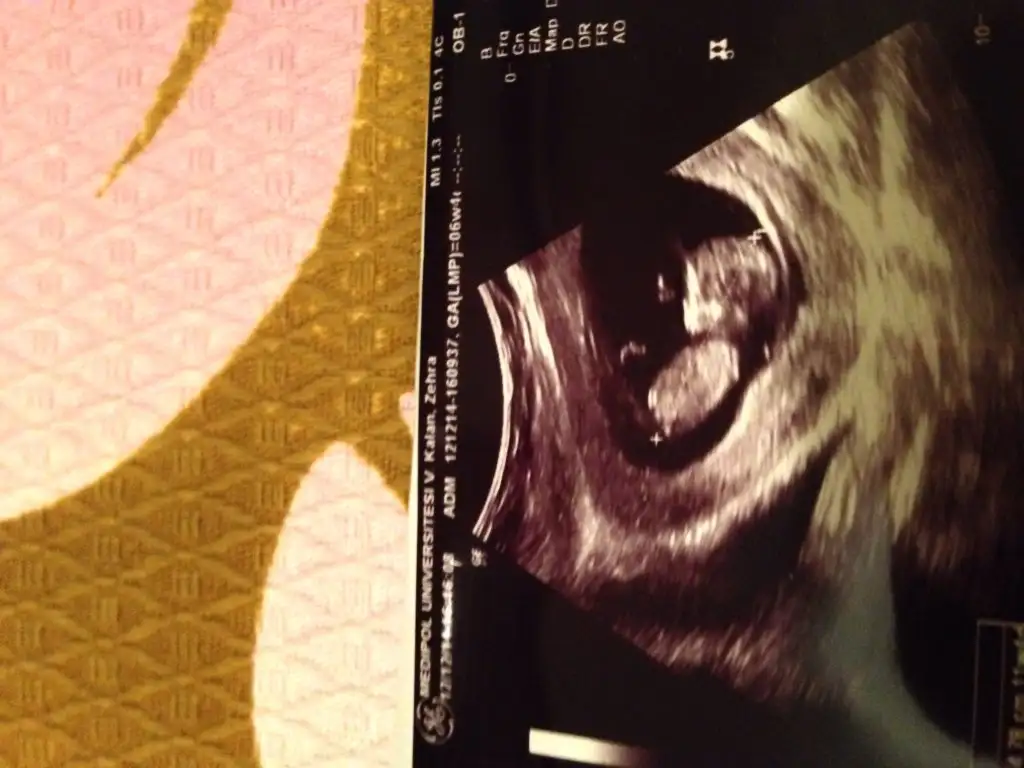

cnm bu haftada anlamak mümkün değil 13 ü bekle bencekızlar ben da 9. haftadayım, nub çıkıntısı varsa da bebişimin bacağı gelmiş sanırım anlamadım, görebilen var mı? :))Eki Görüntüle 1335010

cnm bu fotodo 10 haftalık felan anladığım kadarıyla bu haftada ikisi de aynı nuba sahip göremeyik yani 13 olsun ekle olur muEki Görüntüle 1334521 Eki Görüntüle 1334521